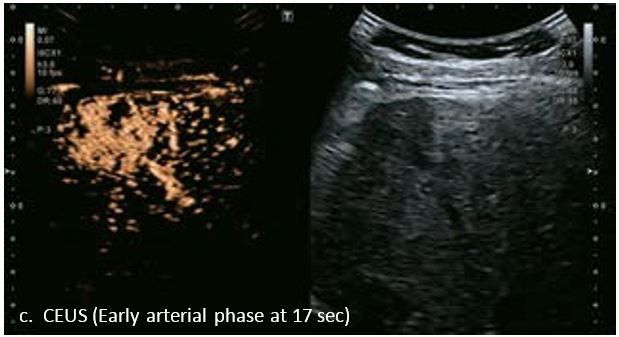

LI-RADS 5 з декількома ГЦК

У 70-річної жінки з цирозом печінки, хворої на вірусний гепатит С, у правій частці печінки виявлено вогнище ураження розміром 23 мм. Детальна судинна структура та підживлююча судина чітко візуалізуються за допомогою CEUS на ранній артеріальній фазі та під час портальної венозної фази, а ураження є ізопідсилюючим. Це ураження є типовим для LI-RADS 5 за своїм розміром, гіперпосиленням в артеріальній фазі та пізнім і помірним вимиванням, що спостерігається через 3 хвилини після ін'єкції.

Малюнок 12